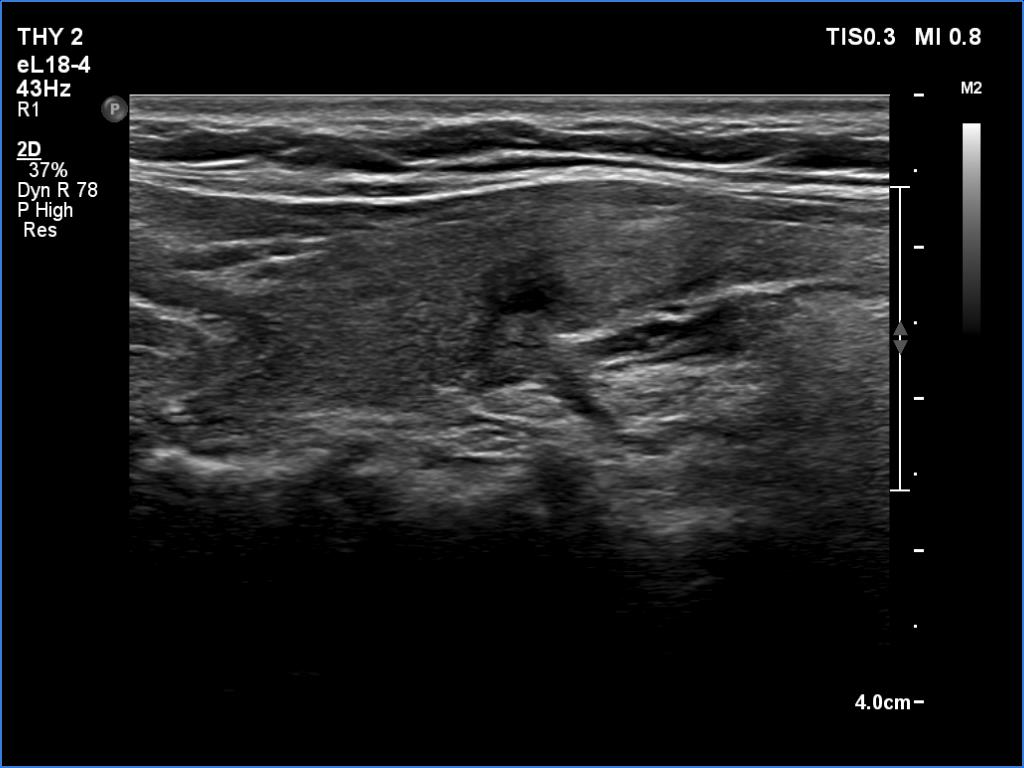

Examination a year after the first visit (third row of images):

Clinical presentation: The patient had no complaints.

Palpation: no abnormality.

Laboratory tests: TSH 2.05 mIU/L, FT4 13.7 pM/L.

Ultrasonography: The ultrasound pattern has normalized. There was a moderately hypoechoic nodule in the right lobe while a cystic lesion in the left one.

Cytology of the right nodule resulted in benign colloid goiter.

Suggestion. Follow-up in two years.